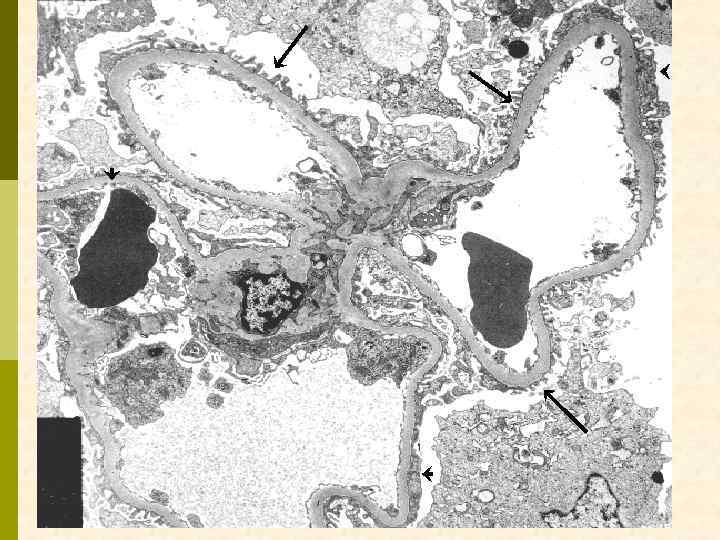

Kidney International, Vol. 7 (1975), p. 111 -122 Focal glomerular sclerosis in nephrotic patients: An electron microscopic study of glomerular podocytes EDITH GRISHMAN and JACOB CHURG Division of Renal Pathology, Department of Pathology, Mount Sinai School of Medicine of the City University of New York, New York Fig. 5. Patient 11: Glomerular capillary wall showing fragmentation of podocyte (FP). I. = capillary lumen (x 15, 250).